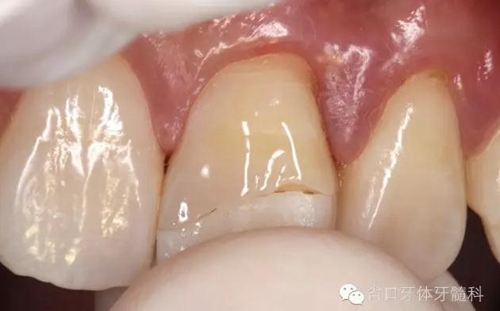

術(shù)前口內(nèi)照

斷冠

折斷之牙體嚴(yán)重脫水,呈白堊色,斷端對(duì)位后吻合度較好,僅少許牙體缺損。